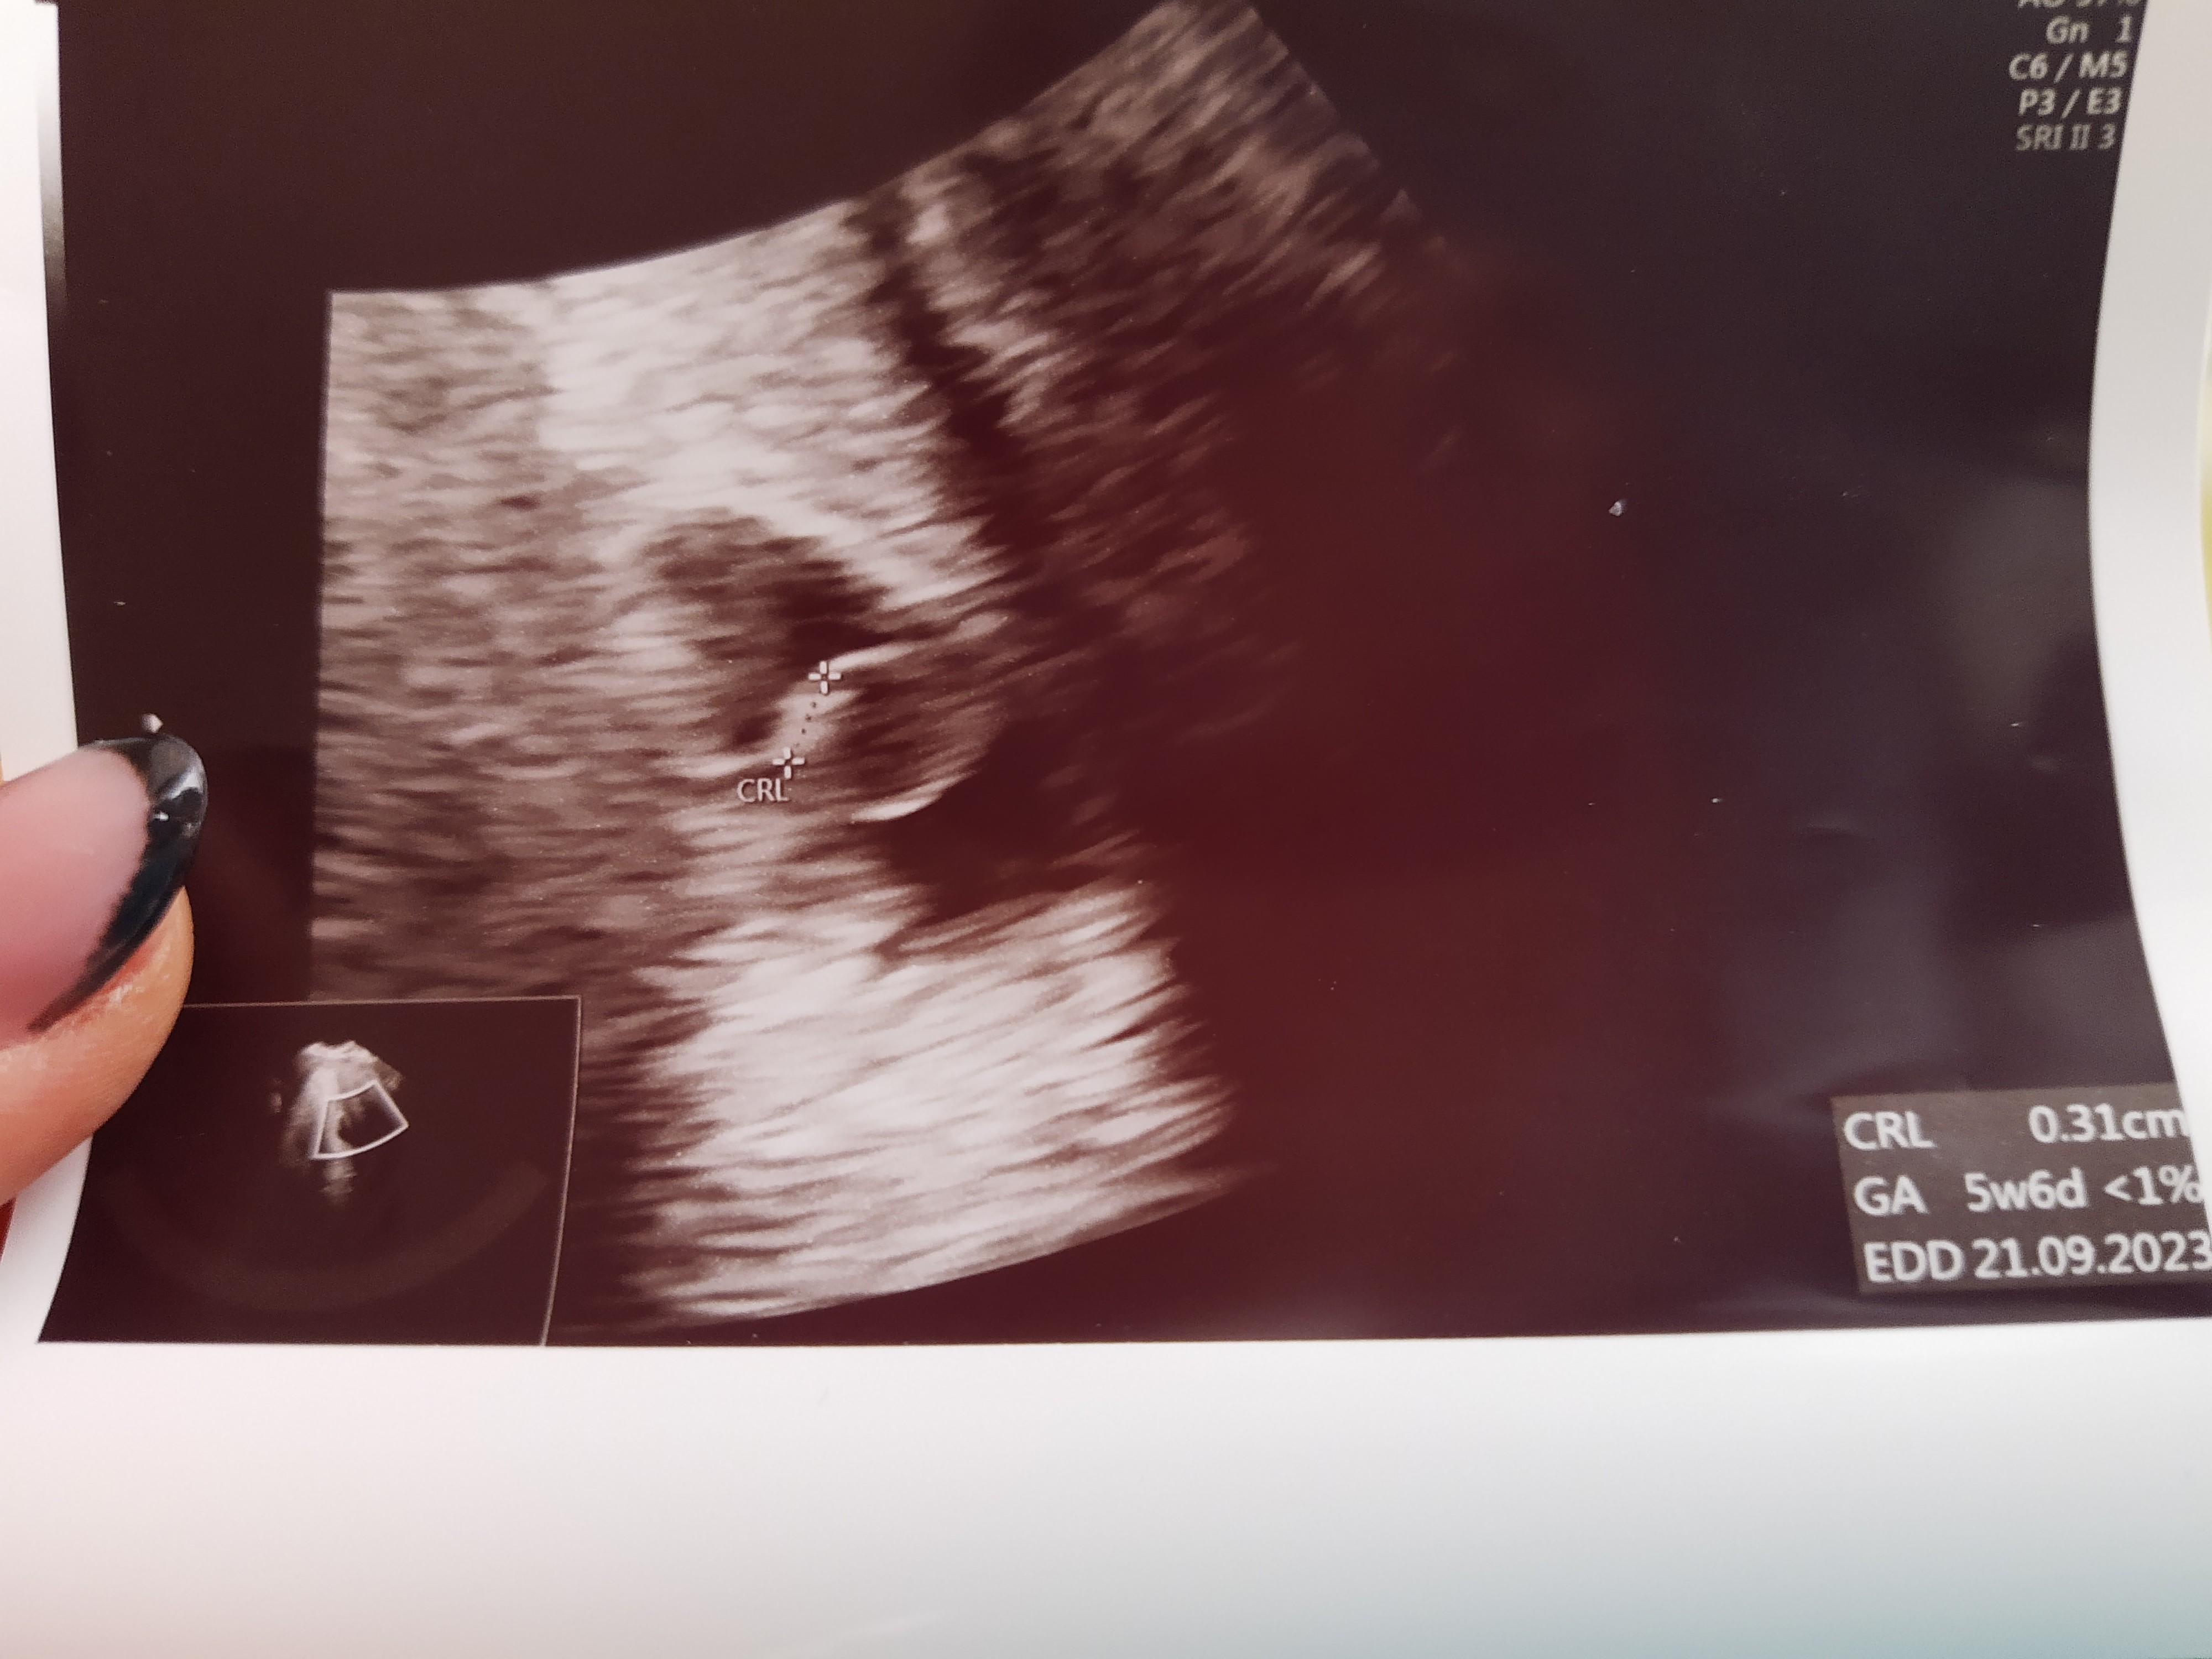

No tu juz widac konkretnie cialko zolte I zarodekA to dzisiaj Zobacz załącznik 1488663

Będzie wszystko dobrze ;-*Jutro 8+2 według OMwizyta o 18:45. Na wizycie 13 stycznia według usg było 6+1 i było już serduszko

Ja dzis 7+6 wiec w sumie jesteśmy w tym samym czasieWitam, dzisiaj ja mogłam dołączyć do grona szczęśliwych i posłuchać bicia serduszka mojego szczęścia.

Dzisiaj byłam na kolejnej wizycie jest serducho i wychodzi na 7+5 tak jak na usg tak wychodzi z om